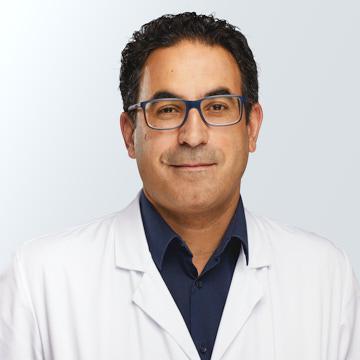

Le Dr Quoc Duy Vo exerce en tant que médecin chef au Service de radiologie de l’EHC depuis le 1er octobre 2019.

Titulaire d’un titre FMH de spécialiste en radiologie diagnostique, le Dr Quoc Duy Vo a effectué sa formation à l’Université de Lausanne (UNIL). Il est titulaire d’un diplôme fédéral de médecine délivré par l’UNIL en 2009, d’un doctorat en médecine de l’Université de Genève (UNIGE) en 2014. Il obtient son titre FMH de spécialiste en radiologie en 2016. En 2021, il réussit l’European board of radiology (EDIR), l’équivalent européen du titre de spécialiste en Suisse.

Le Dr Vo a approfondi son champ d’expertise en imagerie du sein en complétant sa formation avec un diplôme universitaire (Université de Versailles-Saint-Quentin-en-Yvelines) en pathologies du sein en 2015, un diplôme suisse en sénologie en 2016, puis obtient l’EDBI (European diploma of breast imaging) en 2021.

Son expertise s’étend également dans l’imagerie ostéo-articulaire avec l’obtention du plusieurs diplômes universitaires dont le DU d’imagerie d’ostéoarticulaire en 2017 (Université de Montpellier) et le DU d’imagerie en pathologie sportive en 2024 (Université de Lyon). En 2022, il a également obtenu le titre de sous-spécialiste en imagerie ostéo-articulaire avec le diplôme européen EDiMSK (European Diploma of Musculoskeletal Imaging).

Le Dr Vo est également actif dans le domaine du management. En 2021, il obtient le MAS (Master of Advanced Studies) en management stratégique des institutions de santé à l’UNIGE.

En 2024, il achève un doctorat en science des gestion (Executive Doctorate of Business Administration) à la Business Science Institute/Iaelyon – Université Jean Moulin Lyon 3. Son travail de recherche « Impacts d’un changement de logique institutionnelle sur les propositions de valeur dans le business model : le cas de la radiologie en Suisse romande » a permis de mettre en lumière les interactions entre les logiques institutionnelles et les propositions de valeurs dans le domaine de la radiologie. Aussi, il est l’auteur de l’ouvrage Le business model en radiologie pour les managers : Compréhension d’un environnement complexe (2024) – Edition EMS

Il a précédemment collaboré avec l’HFR, en tant que médecin adjoint au service de radiologie diagnostique et en tant que chef de clinique en radiologie au CHUV. Il a également été membre de l’équipe centrale du Centre du sein de l’HFR et chargé de cours à l’Université de Fribourg (Bachelor en médecine).